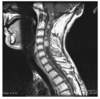

A 34-year-old male presents with a several month history of neck pain, with intermittent episodes of arm and leg numbness. MRI is shown. Which one of the following is most likely?

a. Ependymoma

Ependymomas arise from ependymal cells and

typically occur in the central canal of the spinal

cord, the filum terminale, and the white matter

adjacent to a ventricular surface. They are the commonest intramedullary spinal cord tumor in adults and commoner in males than females (the commonest intramedullary tumors in children are

astrocytoma, ganglioglioma then ependymoma).

The mean age at presentation is 30-40 years with

long duration of symptoms (e.g. 2-4 years). Two

thirds occur in the lumbosacral region (40% of

these arise from the filum terminale (myxopapillary ependymoma). Because of the propensity of these tumors for seeding the craniospinal axis,

CSF evaluation and MRI of the whole craniospinal axis is strongly recommended. The three

main subsets of ependymomas are cellular (this

case), myxopapillary, and anaplastic. Cellular

ependymomas are most often located in the cervical spine. On T1-weighted MRI, they are isointense to hypointense, whereas on T2-weighted MRI, they are hyperintense and there may be a syrinx in 50% of cases. Factors prognostic for a favorable outcome include patient age younger than 40 years; tumors with a lumbosacral location, myxopapillary histologic findings, or a grade of WHO grade I; tumors amenable to GTR or

STR; and good preoperative function of the

patient. Whether volume of residual disease

correlates with a worse outcome after EBRT is

controversial. Most intradural extramedullary

ependymomas are myxopapillary and are often

amenable to complete surgical resection if they

are not multifocal. The goal of surgery is GTR.

Every attempt should be made to remove tumors

as a whole as opposed to piecemeal removal,

because of the risk of seeding, including upward

seeding to the cranial nerves. Typically, complete

resection is achievable in 80-100% of modern

series, with 10-year survival for all spinal cord

ependymomas is 70-100%. Postoperative EBRT

appears to improve local control in patients with

STR ependymomas and also for patients with

high-grade lesions and those with neuraxis dissemination. In most but not all series, the outcome for STR followed by EBRT appears to be

similar to that of complete resection. In patients

with tumors at high risk of seeding, when pretreatment CSF cytologic studies reveal malignant cells, or if the spinal MRI scan shows evidence of leptomeningeal disease, the craniospinal axis should be

treated. There is no strong body of evidence

thus far demonstrating that the addition of

chemotherapy to EBRT improves the outcome,

but it is used in pediatric patients with anaplastic

ependymoma or ependymoblastoma are routinely

given chemotherapy